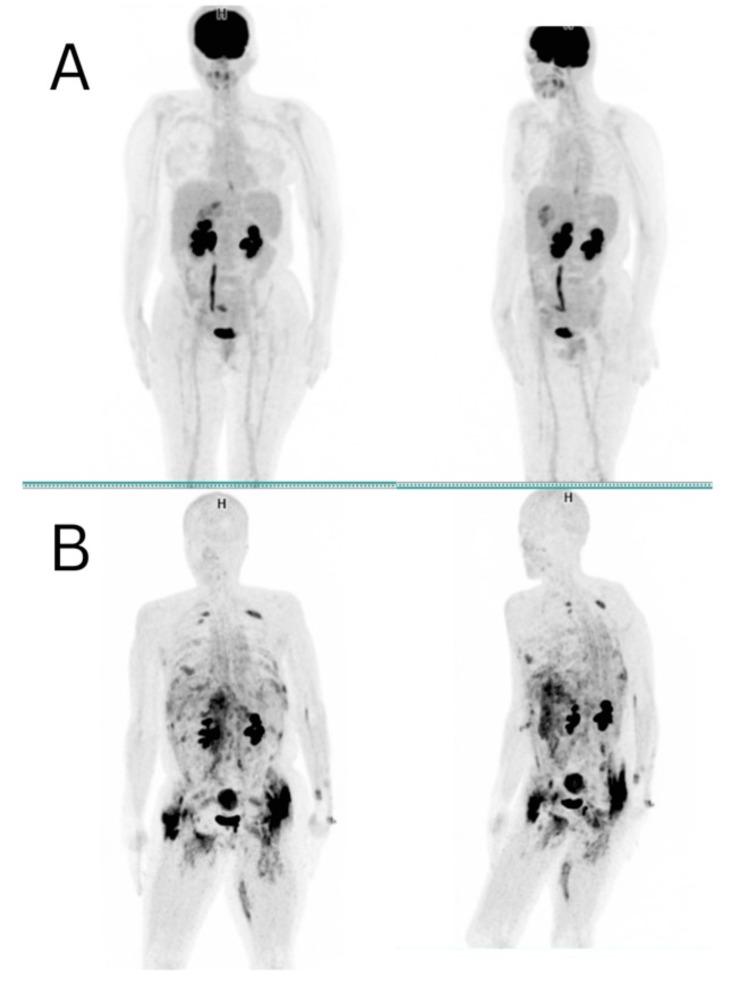

Positron emission tomography/computed tomography (PET/CT) using 18F-fluorodeoxyglucose ([18F]-FDG) is a widely adopted imaging modality for detecting hypermetabolic lesions. However, emerging positron-emitting tracers, such as radiopharmaceuticals featuring fibroblast activation protein (FAP) inhibitors (FAPI) labeled with [18F] or [68Ga], have opened new avenues in nuclear medicine. This case report focuses on the unique behavior of [68Ga]-FAPI in bilateral gluteal myositis ossificans, an infrequent condition characterized by soft tissue ossification. A 45-year-old woman with gastric adenocarcinoma underwent subtotal gastrectomy and received neoadjuvant and adjuvant chemotherapy; [68Ga]-FAPI PET revealed metastatic processes and unexpected [68Ga]-FAPI avid intramuscular ossifications in the pelvic and bilateral thigh muscles. Even though there was no history of trauma, the patient was diagnosed with myositis ossificans, a condition marked by non-cancerous ectopic ossifications. Diagnosis relies on history, radiology, and/or histology. FAPI imaging, increasingly used for inflammatory and infectious diseases, can exhibit uptake in benign conditions, including those involving bones and joints. This case report is the first to document incidental bilateral [68Ga]-FAPI uptake in bilateral gluteal myositis ossificans. The robust [68Ga]-FAPI activity in myositis ossificans highlights the importance of considering myositis ossificans in the context of soft tissue calcifications with intense [68Ga]-FAPI uptake.

使用18F-氟脱氧葡萄糖([18F]-FDG)的正电子发射断层扫描/计算机断层扫描(PET/CT)是一种广泛应用于检测高代谢病变的成像方式。然而,新出现的正电子发射示踪剂,如标记有[18F]或[68Ga]的成纤维细胞活化蛋白(FAP)抑制剂(FAPI)的放射性药物,为核医学开辟了新途径。本病例报告重点关注[68Ga]-FAPI在双侧臀肌骨化性肌炎中的独特表现,这是一种以软组织骨化为特征的罕见病症。一名45岁的胃腺癌女性患者接受了胃大部切除术,并接受了新辅助和辅助化疗;[68Ga]-FAPI PET显示有转移过程以及盆腔和双侧大腿肌肉中出现意外的[68Ga]-FAPI摄取增加的肌内骨化。尽管没有创伤史,但该患者被诊断为骨化性肌炎,这是一种以非癌性异位骨化为特征的病症。诊断依赖于病史、放射学和/或组织学检查。FAPI成像越来越多地用于炎症和感染性疾病,在包括涉及骨骼和关节的良性病症中也可表现出摄取增加。本病例报告首次记录了双侧臀肌骨化性肌炎中偶然出现的双侧[68Ga]-FAPI摄取。骨化性肌炎中强烈的[68Ga]-FAPI活性突出了在具有强烈[68Ga]-FAPI摄取的软组织钙化情况下考虑骨化性肌炎的重要性。